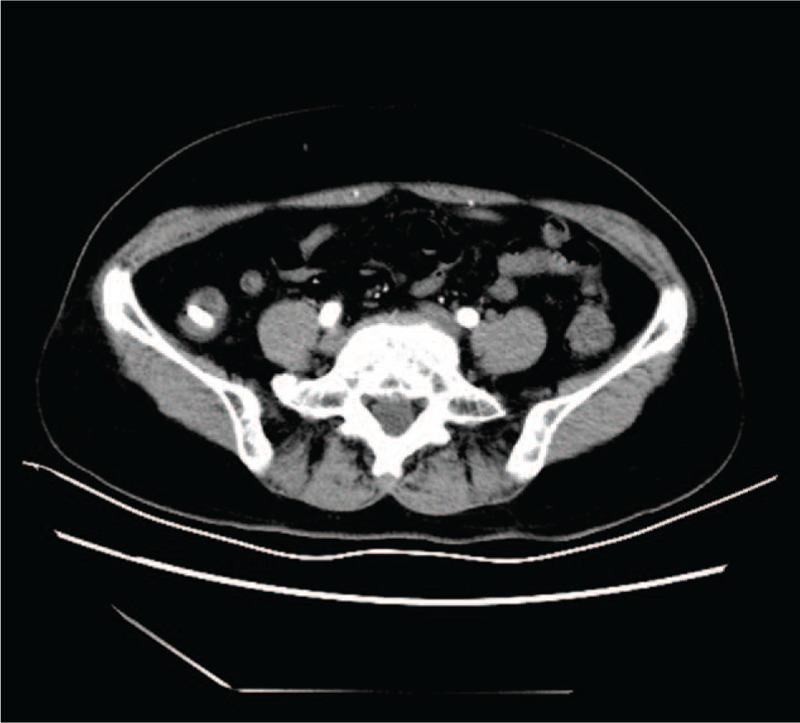

This review presents the case of a female patient complaining of recurrent abdominal pain in the right lower quadrant, similar to the clinical symptoms of appendicitis. Physical examination revealed an abdominal tenderness in the right lower quadrant without rebound tenderness or muscular tension. An ultrasound examination found a mass located in the right lower abdomen. Computed tomography showed a high-density shadow in the cecal cavity.

本病例报告了一名女性患者,主诉右下腹反复疼痛,与阑尾炎临床症状相似。体格检查发现右下腹压痛,无反跳痛或肌紧张。超声检查发现右下腹有一肿块。计算机断层扫描显示盲肠腔内有高密度影。